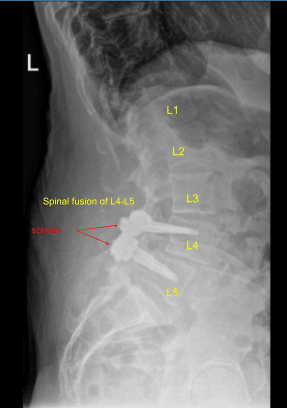

Case Study: Posterior Spinal Fusion L4-5 (Instrumented) with L3-5 decompression

Prior physical examination of the lumbar spine supported the diagnosis of lumbar canal stenosis. His imaging showed grade 1 to grade 2 spondylolisthesis with instability over L4-L5 with compression of nerve roots. There is also lateral recess compression at L3-L4 on the right and left side with compression of the traversing L4 nerve root.

Spinal Fusion of L4-L5